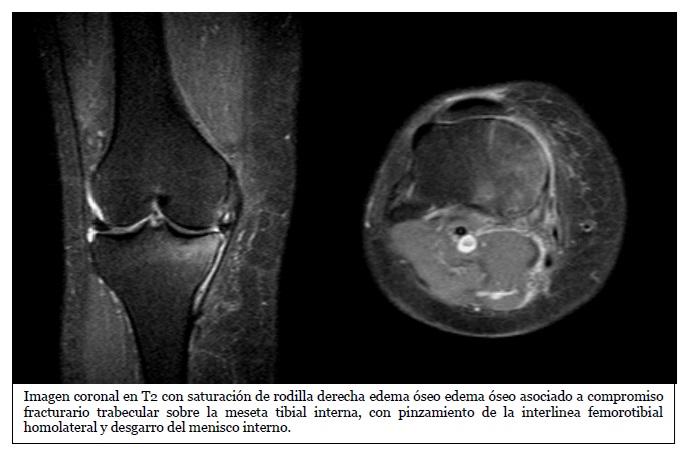

La mayoría de los casos de edema óseo en la rodilla están asociados con lesiones de tejidos blandos. Esto sugiere que el edema óseo generalmente ocurre como una respuesta secundaria a una lesión más amplia en la rodilla, que puede incluir daños en los ligamentos, tendones, meniscos o músculos. Esta alta asociación puede indicar que, al detectar edema óseo en una RM, es crucial investigar y evaluar las posibles lesiones de tejidos blandos para un diagnóstico completo y preciso.

La mayoría de los casos de edema óseo están asociados con lesiones en el menisco medial (70% de los casos). Esto sugiere que el menisco medial es más susceptible a lesiones que resultan en edema óseo. Las lesiones en esta área pueden ser más comunes debido a su función en la estabilización de la rodilla y la distribución de cargas durante actividades físicas.

Otro aspecto relevante consiste en destacar la importancia de la RM de rodilla en las lesiones meniscales; son causa de edema óseo, ya sea aisladas o en asociación con otras lesiones, como pueden ser alteraciones condrales o lesiones en el LCA, las roturas de cuerpo y cuerno posterior, las lesiones en rampa y las roturas de raíz son lesiones meniscales que pueden asociar edema óseo y que el radiólogo debe conocer.